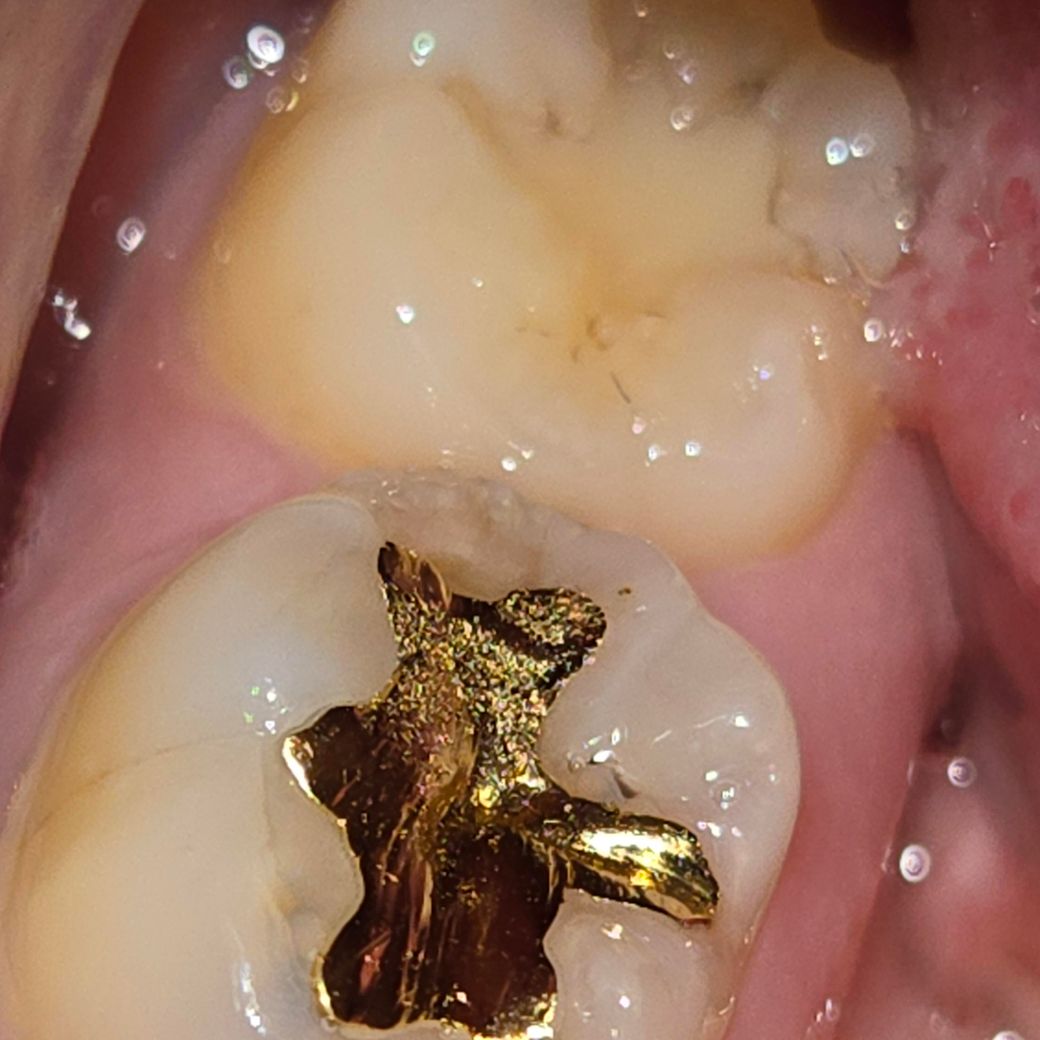

치과에서 원인은 모르겠다고 했는데 이빨이 아파요

금으로 떼운 이빨이 아파서

거울로 보기에는 이빨에 검은 점이나 줄 같은게 몇개 보여서요

떼운 이빨 위쪽에 약간 회색으로 된 부분이 아픈 것 같아요

• 1번 째 사진

씹을 때나 양치할 때만 그런다면 치아 주위 잇몸에 염증이 있을 경우 그런 증상이 나타나기도 합니다.

아니면 금으로 떼운 것 안쪽에서 문제가 생겼을 가능성도 있으며, 이럴 경우에는 금으로 떼운 것 제거하는 수밖에 없으니 조금 더 지켜보는 것을 추천합니다.

금으로 치료한 치아가 씹을때 아픈경우라면 치아에 금이갓을 가능성이 높습니다. 많이 불편하시면 신경치료를 해야될수도 있습니다.

치아 크랙이 사진상, 증상으로 봤을때 의심됩니다 지속적으로 증상발생 시 크라운을 해주어야 할 수도 있습니다 평소 딱딱하거나 질긴음식을 즐겨 먹었다면 가능성이 더 높습니다